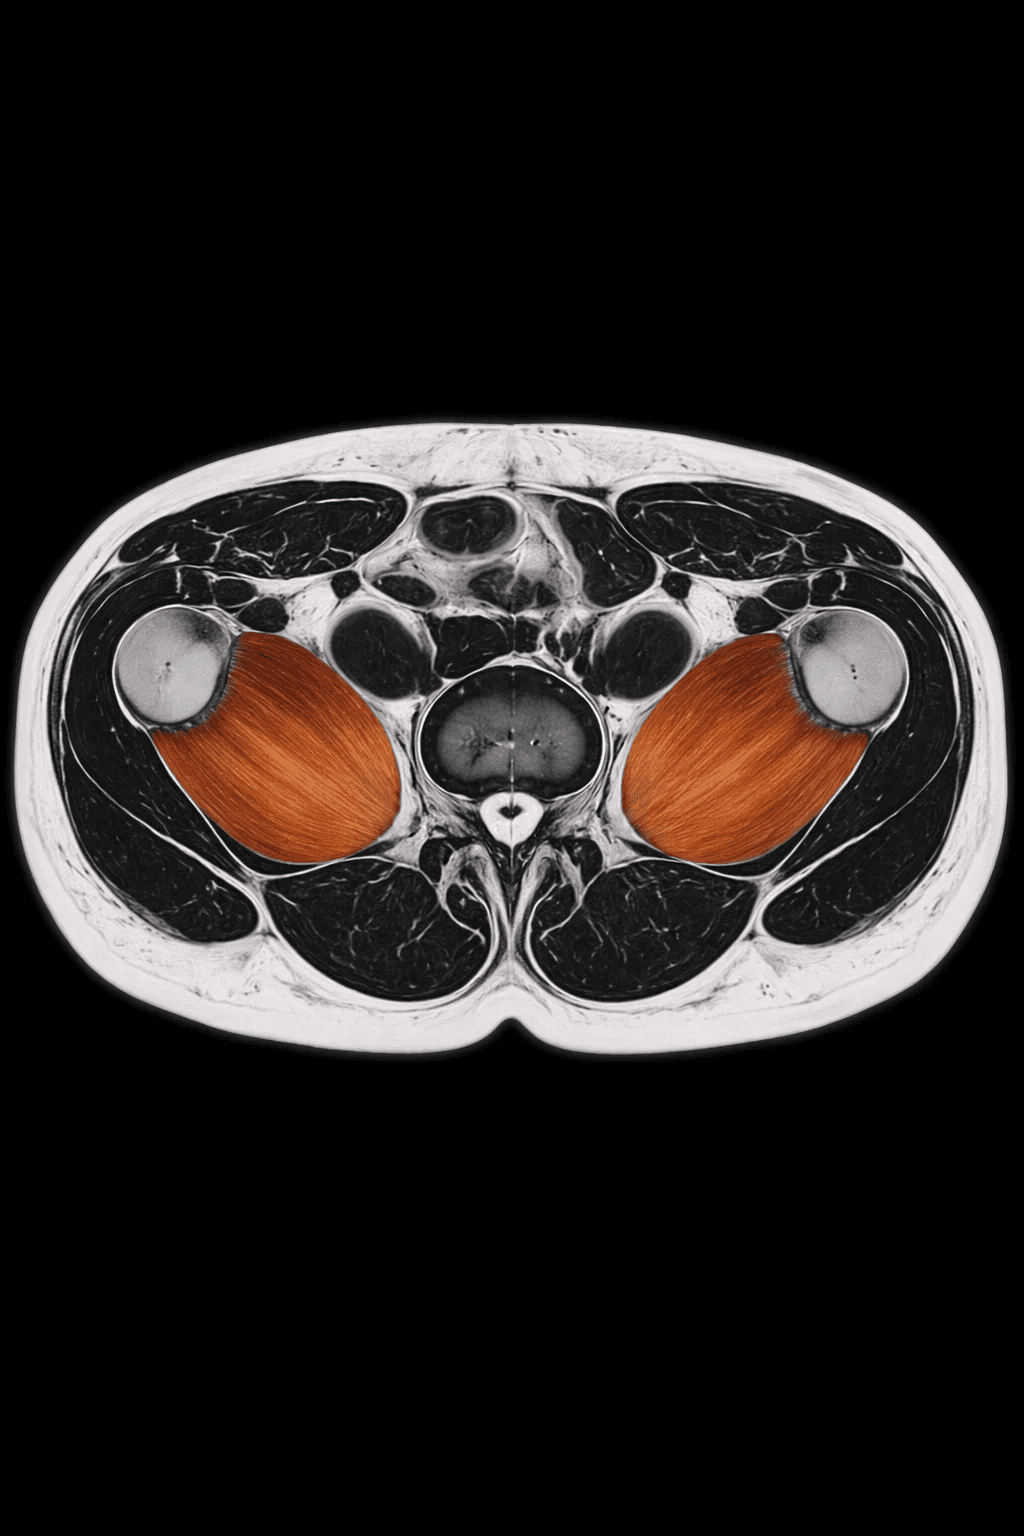

MRI Psoas Muscle Quantification is an advanced imaging analysis that measures the size, volume, and quality of the psoas muscles, the deep core muscles essential for posture, stability, and movement. These muscles serve as a powerful biomarker of overall muscle health and physiological resilience.

The assessment quantifies muscle cross sectional area, symmetry, and tissue composition. It detects muscle depletion, fatty infiltration, and imbalances that may not be visible externally.